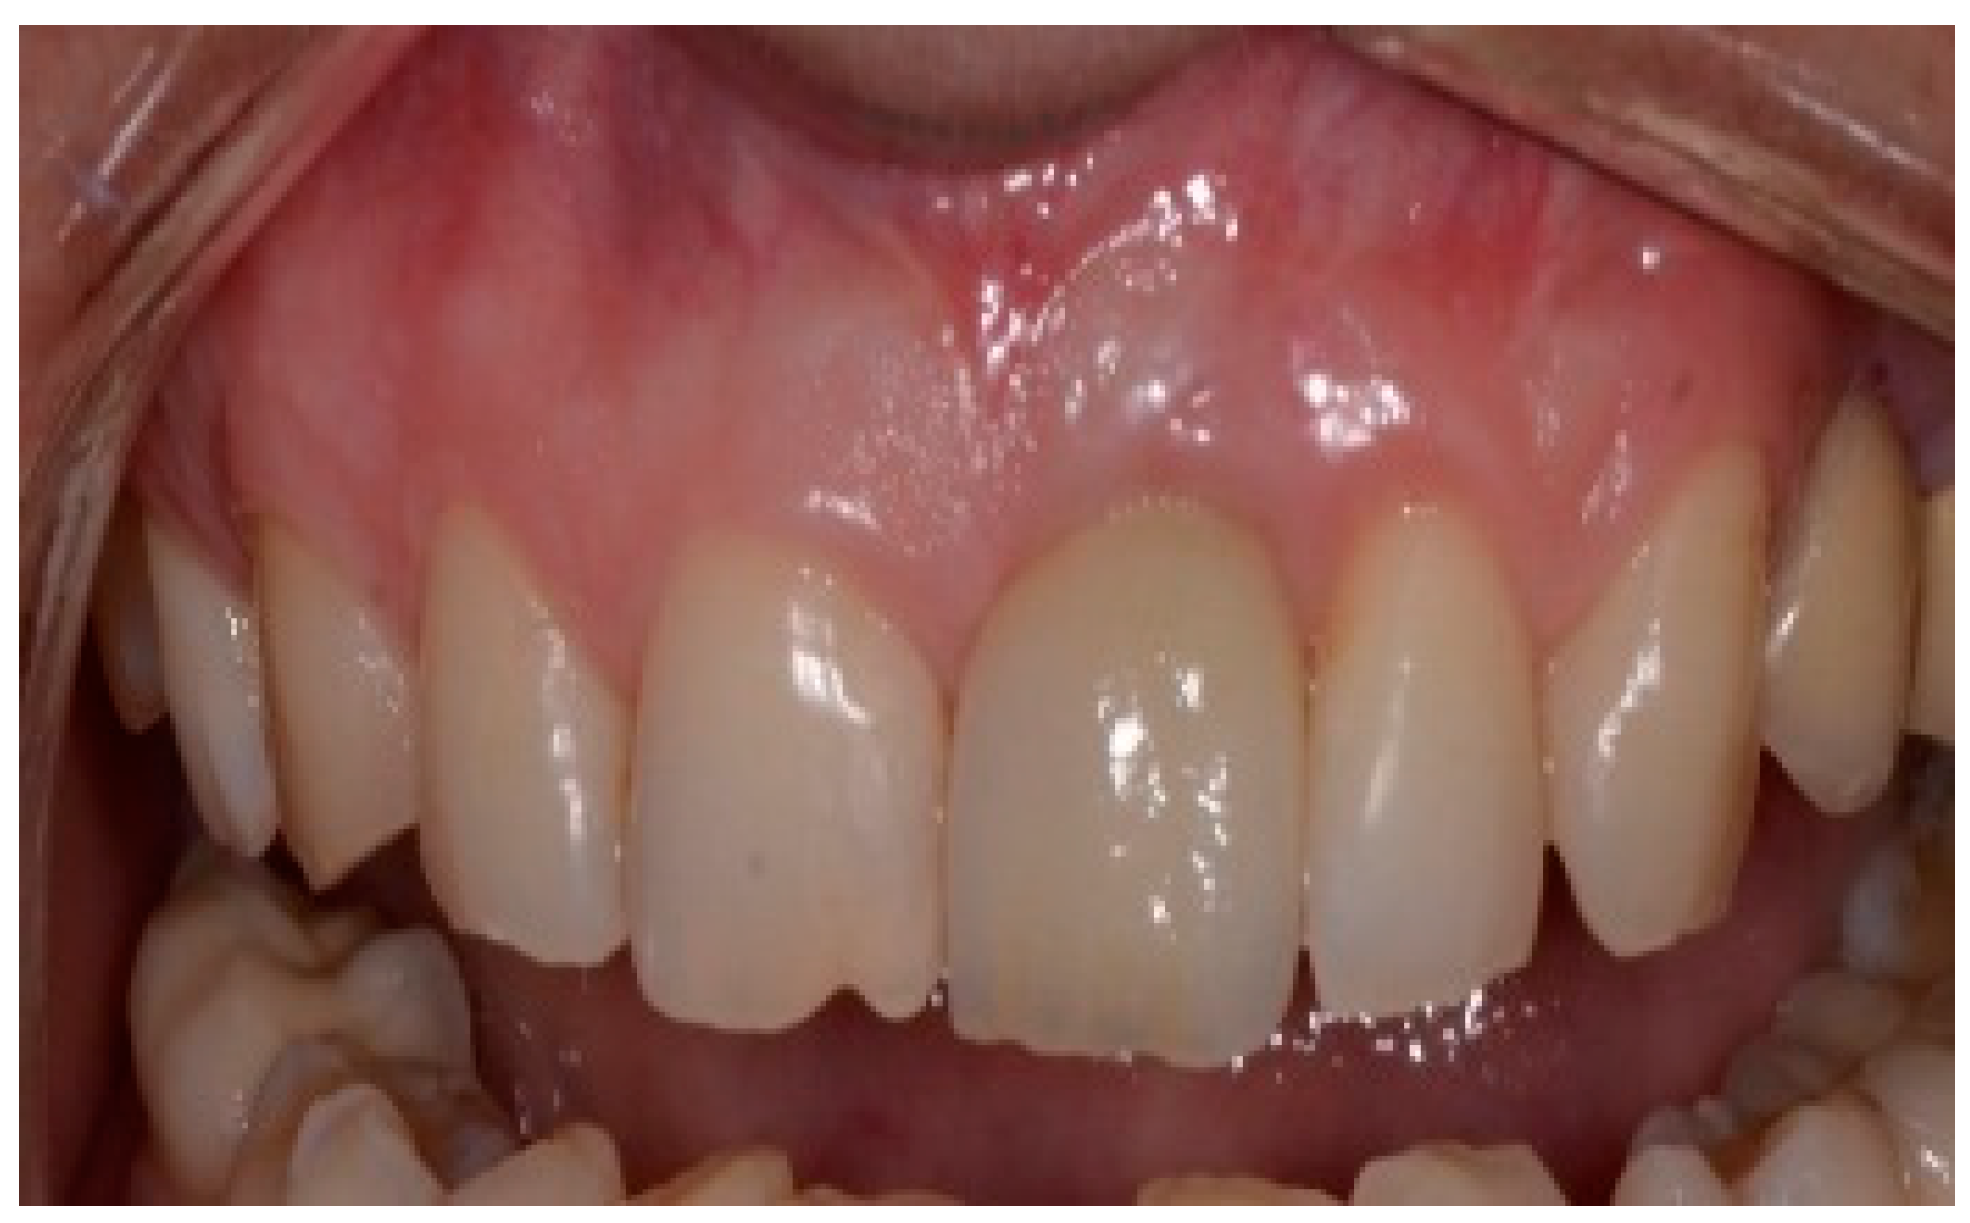

Following a 6-month healing period (Figure 6), definitive prosthetic rehabilitation was carried out using zirconia CAD CAM abutments (Straumann, Andover, MA 01810, USA). The ceramic zirconia crowns of teeth 8 and 9 were placed (Figure 7). At the two-year follow-up examination for patients #1 and #3 and three-year for patients #2 and #4, the implants were fully osseointegrated, presenting satisfactory functional and esthetic conditions without clinical or radiographic signs of any pathology.

Figure 7.

Clinical view of final ceramic crowns on teeth 8 and 9.

Aesthetic implant restorations are defined as those that resemble natural teeth in different aspects [16]. The placement of an implant prosthesis in the maxillary anterior region is particularly challenging due to the high esthetic demands and complex anatomical considerations. Several factors influence the esthetic outcome of immediate implant placement. These risk factors should be thoroughly discussed with the patient before initiating treatment to manage expectations and prevent post-treatment dissatisfaction. Esthetic risk factors can be classified into two main categories: clinician-related factors and patient-related factors. Clinician-related factors included improper implant placement (position and angulation), improper selection of implant diameter, and poor soft and hard grafting techniques. Patient-related factors include the periodontal phenotype (thin tissue, deficient facial bone, and soft tissue), presence of infection, interproximal bone height, previous adjacent restorations, edentulous space size (mesio-distal dimension of the extraction site), and previous surgeries. Despite following the established surgical protocol for immediate implant placement—such as positioning implants in a lingual position along the long axis of the adjacent tooth, maintaining a 2 mm gap from the socket wall, placing implants 1.5 mm below the bone crest or 3 mm below the free gingival margin, and using a slow-resorbing bone graft—the esthetic outcomes in two of the presented clinical cases (Case 1 and Case 3) were clinically acceptable but not ideal. The aesthetic outcomes of these two cases were negatively affected by (a) the presence of scar tissue due to repeated periodontitis (crown lengthening and apicoectomy), (b) the uneven gingival margin, (c) a wide interdental space, (d) the interproximal space height > 5 mm (crest of the bone to contact point), and (e) prosthetic design.